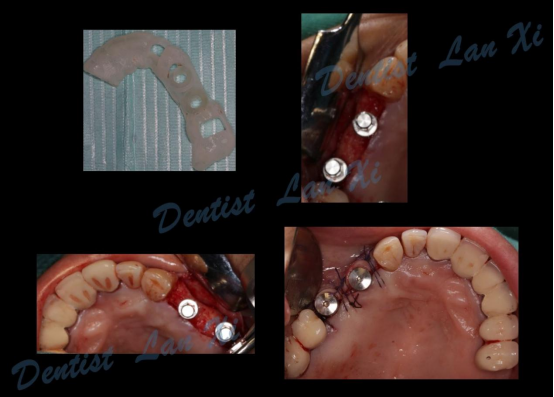

第四步:导板制作完成

(目前生成导板的方式主要有3D打印和切削两种方式)

第五步:外科手术

二、精准控制 更安全

在数字化种植导板下的外科手术更加精准。种植体植入方向、位置、角度、深度等一目了然,即可将种植体精准植入到最佳位置,获得更优异的临床效果,手术安全性更高。

三、过程引导 更微创

数字化种植导板将术前设计方案精准转移,保证了种植体植入位置、方向及角度等的精确性,同时充分利用余留骨量,减少甚至避免了附加手术。